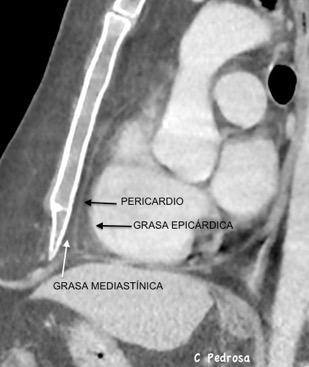

84. ENSANCHAMIENTO MEDIASTÍNICO CON GRASA

1. Lipomatosis difusa

S. de Cowden

Proteus/Cloves

Enf. de Dercum

En. de Madelung

Inducida por drogas

Lipomatosis difusa

Esteroides/Retrovirales

Familiar difusa

Landis MS et al. Radiology 2009

111. LIPOMATOSIS MEDIASTÍNICA

151. TRAQUEOPATÍA OSTEOPLÁSTiCA